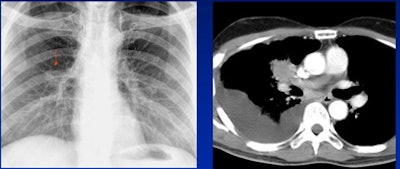

| Satisfaction of search error: The reader found the pacemaker but missed the lung mass behind it. |